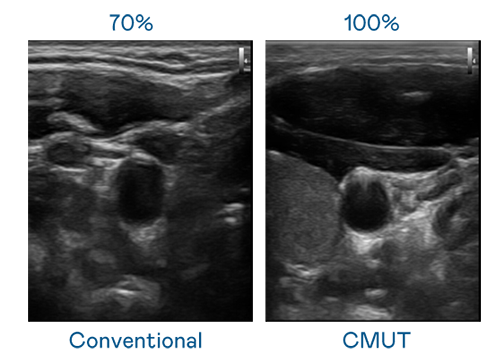

CMUT 技术是一种用电容式微机电元件来产生超音波讯号的技术。与传统 PZT 压电式技术相比,CMUT 频宽增加 30%,更宽频的超音波讯号让影像解析度大幅提升,是实现高影像品质医疗超音波扫描、促进精准医疗发展的关键技术。

大频宽带来超清晰影像

超音波影像的解析度高低,首先取决于探头能发出的讯号频宽。3377体育 CMUT 可提供高清晰的超音波讯号,提供高频宽、高灵敏度、影像纹理细节更高的超音波影像,协助医护人员缩短影像判读时间及利用精准的医疗影像进行诊断。